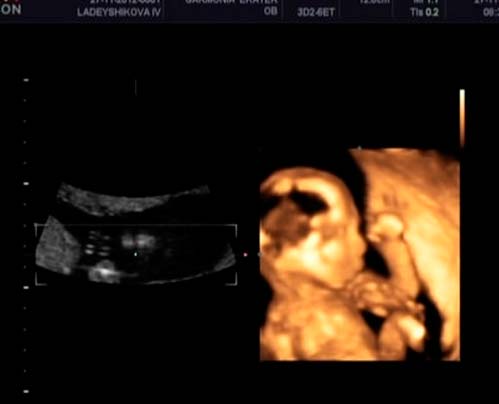

If you have not previously been tested for hCG, AFP and free estriol hormones (to identify possible pathologies), your doctor will prescribe them this week. The same goes for ultrasound.On an ultrasound scan, in addition to the basic parameters of your baby, you can find out the gender of the future baby.

An ultrasound specialist will conduct a very thorough examination of the fetus. It will determine the overall dimensions, as well as the circumference of the head and the length of the arms and legs. The doctor will definitely compare them. In addition, all internal organs, the condition of the heart and major vessels, plus the location of the placenta, will be checked.

The position of the baby in the uterus is not yet important. Before childbirth, he may more than once roll over.

Ultrasound photo (clickable)